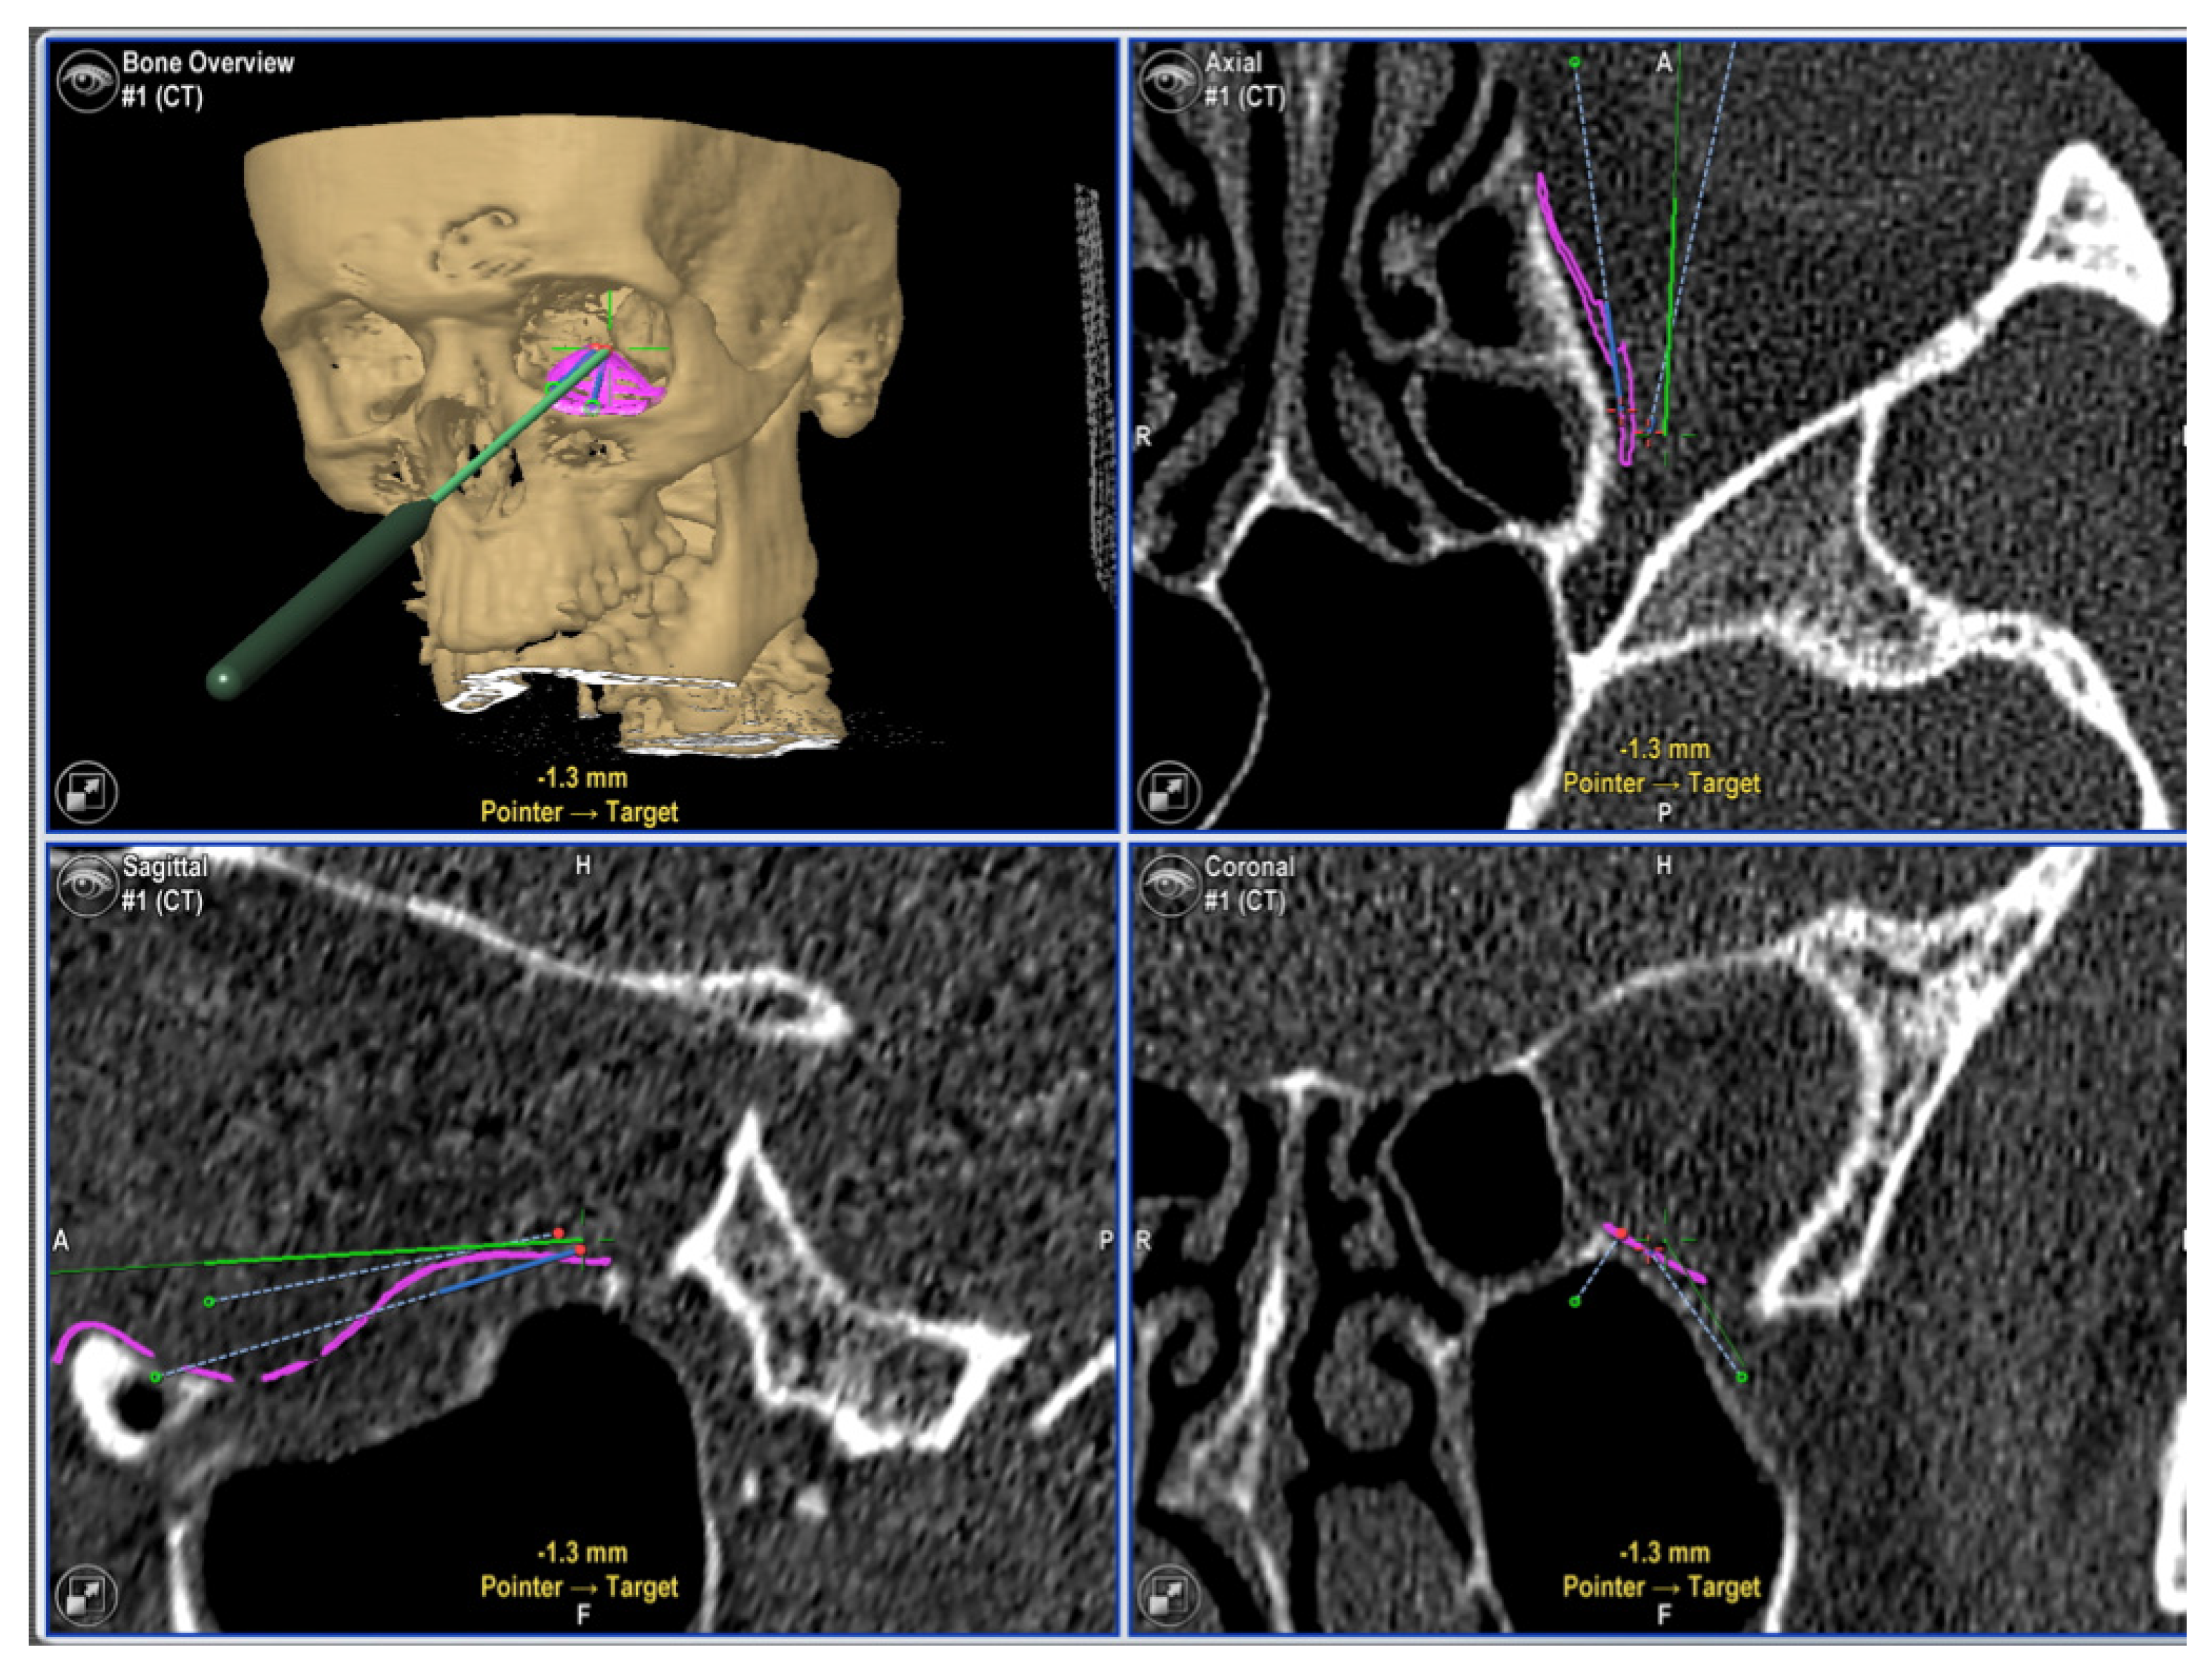

- Rana, M.; Chui, C.H.K.; Wagner, M.; Zimmerer, R.; Rana, M.; Gellrich, N.-C. Increasing the accuracy of orbital reconstruction with selective laser-melted patient-specific implants combined with intraoperative navigation. J. Oral Maxillofac. Surg. Off. J. Am. Assoc. Oral Maxillofac. Surg. 2015, 73, 1113–1118. [Google Scholar] [CrossRef] [Green Version]